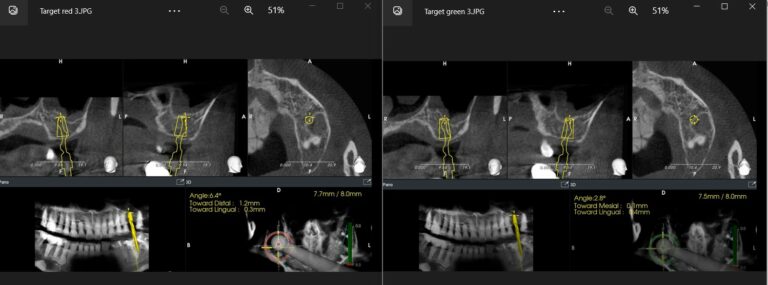

To the left, the implant drill is almost in it’s final depth (7.7/8 mm) yet the angle deviation is at 6.4 degrees. Seeing the red indicator in the navigation system, the operator can now correct the angle accordingly, until the indicator turns green (right side, angle corrected to 2.8 degrees)

Now, one might wonder if this setup really makes sense, as you cannot modify the position of the implant through the surgical guide. Well, you actually can. Remember we said that one common source of deviation is the elasticity of the surgical guide, combined with the “leeway” or gap between the sleeve and the drill and the operator’s ergonomic position. Now using the dynamic system helped realise such an error in real time and compensate for it. We found that particularly important in correcting the angle. You see, the leeway of the surgical guide can still allow for angle deviation of as much as 7-8 degrees, even when the drill has reached its final depth, without the operator being aware of it. By visualizing this error, the operator could correct accordingly thus reducing significantly the final deviation.